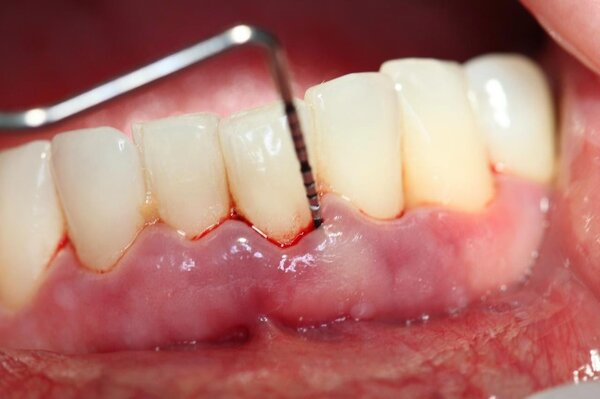

Nhiễm trùng nướu là dấu hiệu phổ biến nhất của trường hợp niềng răng không thành công. Khi mà tác động lực quá nhiều lên răng và nướu hoặc sử dụng các dụng cụ không sát trùng khiến cho nướu bị viêm, sưng và nếu như không chữa trị kịp thời thì sẽ khiến cho bạn bị viêm nha chu, gây đau nhức và khó chịu.

Các vấn đề về nha khoa mà bạn gặp phải trong quá trình niềng răng nhưng không được chữa trị kịp thời như nhiễm trùng nướu, viêm nha chu cũng là nguyên nhân khiến cho ca niềng răng của bạn thất bại.

Thêm một nguyên nhân khiến niềng răng không thành công đó là thiết bị chỉnh nha của nha khoa kém chất lượng, không đảm bảo vô trùng khiến cho bạn bị các vấn đề như viêm nha chu, viêm nướu hoặc các thiết bị tác động lực quá lớn khiến răng bạn bị lệch.